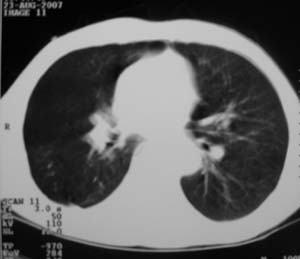

男,54岁,无任何不是感.体检发现右肺部阴影.现行ct进一步确诊.

右侧胸廓塌陷,肋间隙变窄,肋骨增生变粗,脏壁层胸膜肥厚、钙化。符合陈旧性结核性脓胸改变

右侧包裹性积液伴胸膜钙化.

右侧包裹性积液并胸膜钙化,性质还是结合穿刺细胞学检查的好,结核性、化脓性均会有钙化。

右侧胸膜肥厚、粘连、钙化。

周围都钙化了应该不是积液了吧,这样都没有不适感,病史不详